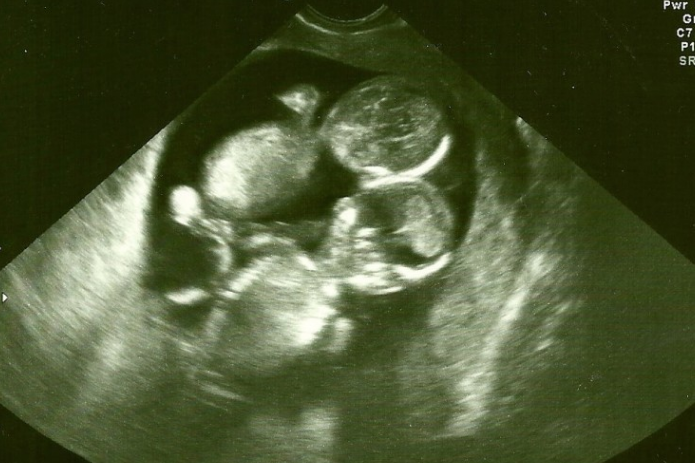

▼热爱小孩的凯特和丈夫领养了两个小孩,不过她仍然希望可以靠自己的力量生出孩子。当难以受孕的她好不容易怀孕时,就赶紧去找医生检查,医生比出2根手指表示她怀了双胞胎时,凯特简直开心死了!

▼生产当天凯特跟家人都无比紧张,当医生剖开她的孕肚时,却看到了相当不可思议的场景:新生双胞胎的脐带紧紧缠绕着,就像一条错综的麻花辫!但它并没有阻碍宝宝摄取养分,两位小女婴都顺利生下来了!